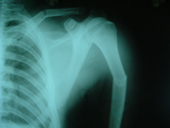

| Fracture Humerus |

Fracture humerus post op |